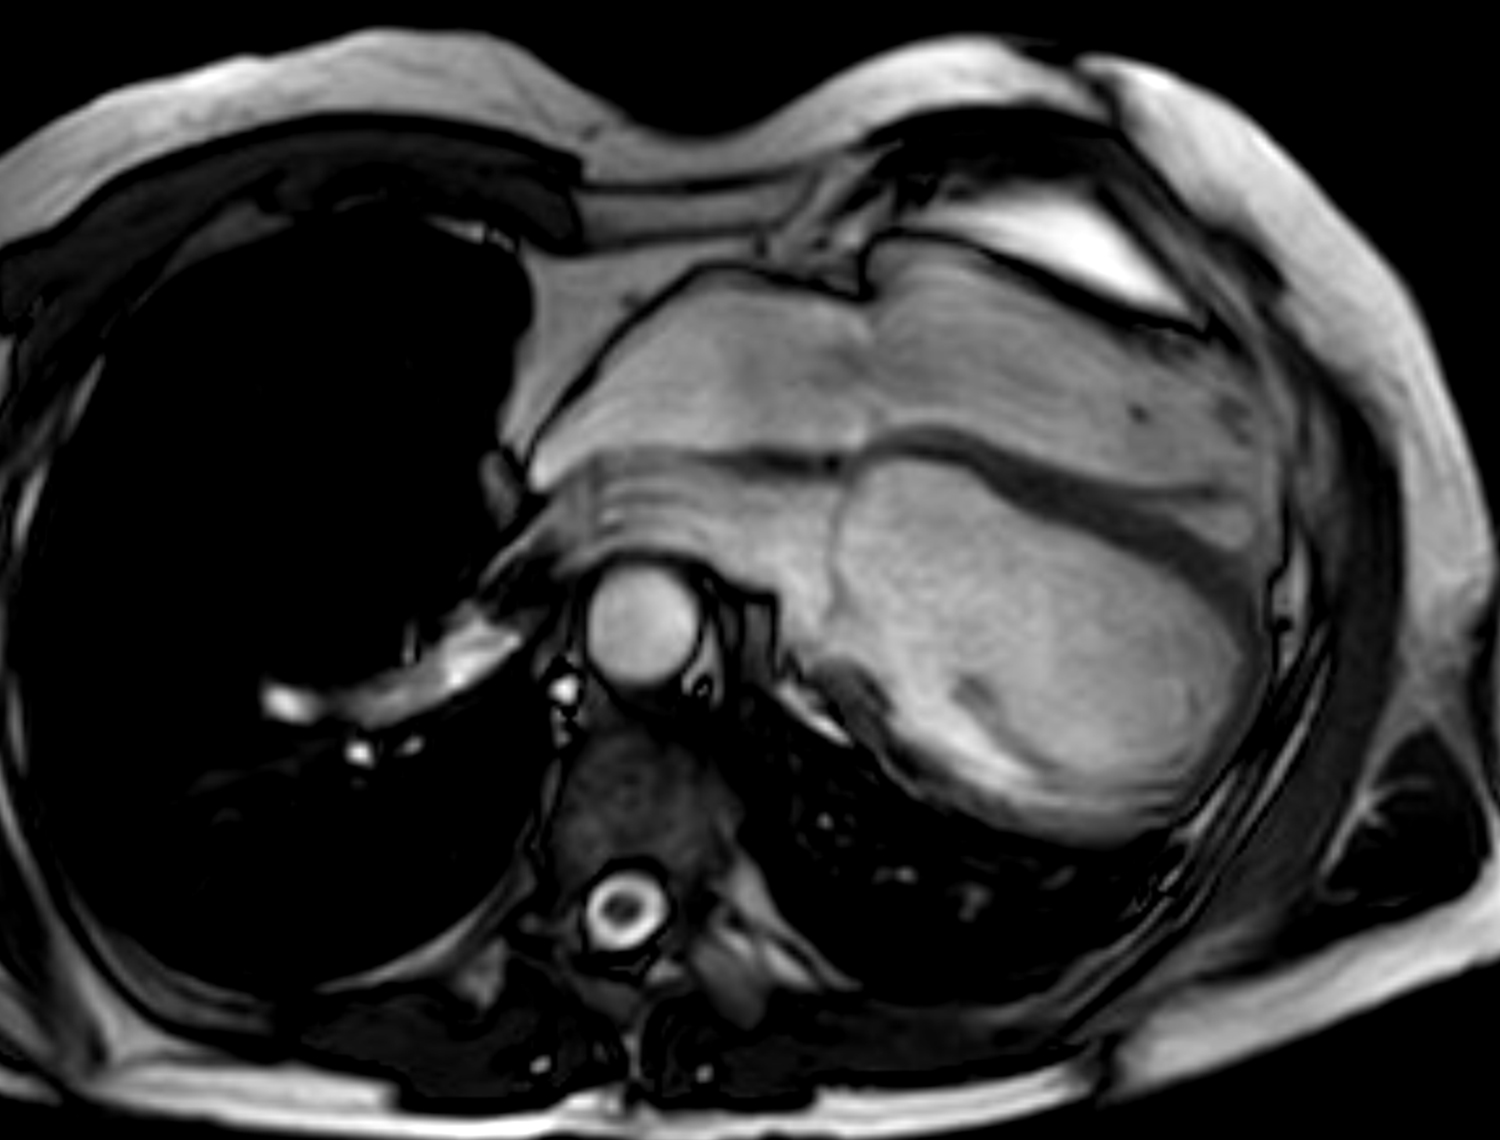

Congenital absence of the pericardium is a rare anomaly involving partial or complete absence of one or both sides of the pericardium, and complete left-sided absence being the most common [75, 76]. In a minority of patients there are associated other congenital heart diseases such as atrial septal defect and tricuspid atresia [77]. It is often an incidental finding in asymptomatic patients either on imaging (chest or cardiac) or during cardiothoracic surgery, although symptoms may include atypical chest pain, dyspnea, palpitations and dizziness. When echocardiography is performed, typical findings include unusual imaging windows, apparent right ventricular dilation, systolic paradoxical septal motion and excessive cardiac motion [75, 78]. CT and MRI provides direct visualization of its characteristic features in both axial and reconstructed views, such as leftward posterolateral displacement of the apex (levorotation – Fig. 6) and lung tissue interposition in unexpected locations (e.g., between base of heart and diaphragm, between aorta and pulmonay artery) [75]. High-risk imaging findings that may pre-dispose sudden death are left atrial appendage or other chamber herniation and strangulation, left ventricular hinge point or crease, and coronary artery compression or inducible ischemia on stress perfusion [76].

Fig. 6.Congenital absence of the pericardium on magnetic resonance imaging (axial slice steady state free precession bright blood sequence).